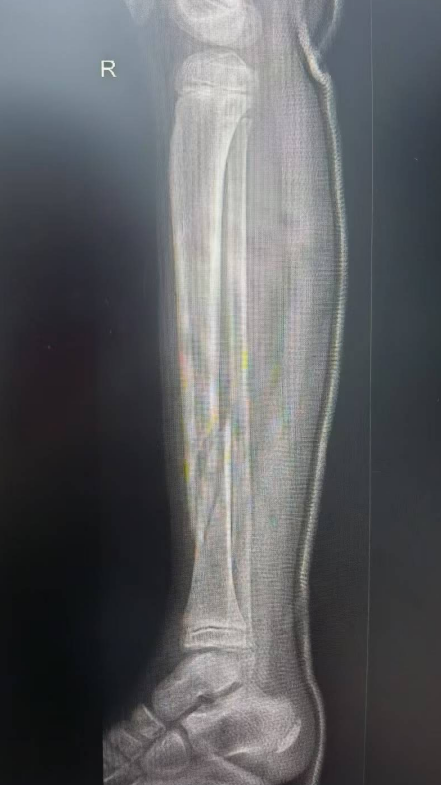

如5岁男童瑞瑞踩着平衡车从广场边缘台阶上摔下,导致左臂肱骨髁上骨折;6岁女童萱萱骑滑板车避让障碍物失去平衡,重重摔倒,造成胫骨骨折。

桡骨远端骨折,通过手法复位